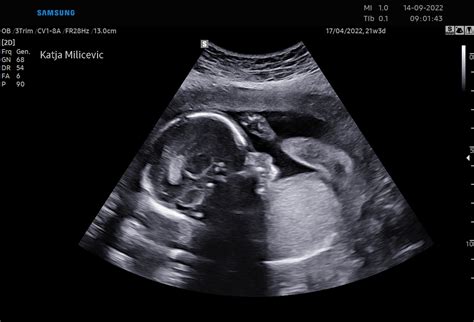

V 25. tednu nosečnosti vaš otrok od temena do trtice meri približno 22 cm in tehta okoli 700 g. Kljub temu, da je še majhen, se njegov razvoj odvija z neverjetno hitrostjo. Vaš otročiček začenja dobivati rožnato barvo, saj se pod kožo oblikujejo kapilare, ki se polnijo s krvjo. Ta proces je ključen za pravilno cirkulacijo in oskrbo telesa s kisikom.

Zaradi vedno boljše koordinacije lahko otrok zdaj stisne pest ali z rokami seže proti stopalom. Te drobne motorične vaje so pomemben del njegovega razvoja, saj krepijo mišice in izboljšujejo nadzor nad telesom. Njegova pljuča se pripravljajo na prvi vdih in še naprej proizvajajo surfaktant, ki bo po rojstvu pripomogel k normalnemu delovanju pljuč. Surfaktant je snov, ki preprečuje, da bi se pljučni mešički po izdihu zlepili skupaj, kar je bistveno za učinkovito dihanje. Medtem se razvijajo tudi živci okoli otrokovih ust, kar bo v prihodnosti omogočilo sesanje in hranjenje.

Sluh vašega otroka je napredoval in zdaj morda že lahko prepozna tudi glas vašega partnerja. Zvoki iz zunanjega sveta postajajo vse bolj pomembni za njegov razvoj, zato je pogovor z otrokom skozi trebuh lahko koristna praksa.

Nevrologi in pediatri poudarjajo, da se v tem obdobju otrok že "vadi" za življenje zunaj maternice. V tem tednu plod pridobi nekaj podkožne maščobe, kar pomaga pri uravnavanju telesne temperature po rojstvu. Nagubana koža se bo počasi pričela pomikati nazaj, saj jo bo napolnila podkožna maščoba, kar bo otroku dalo bolj zaokrožen videz, podoben novorojenčku.

Pomembna novost v tem tednu je, da plod postaja vse bolj podoben novorojenčku. V tem tednu je plod deležen pospešene rasti las, kar velja tako za plod kot za nosečnico - obe imata v 25. tednu gostejše in polnejše lase. Hormonske spremembe, ki vplivajo na to, so še vedno prisotne in njihov vpliv bo opazen še nekaj tednov po porodu.

Od tega tedna naprej dojenček dobiva občutek za ravnotežje. Med obračanjem v trebuščku se že zaveda, ali je z glavico obrnjen navzdol ali navzgor. Hkrati pridobiva vedno več maščobe in tudi las. V tem stanju znotrajmaterničnega razvoja lahko dojenček prvič odpre očesa. Poleg tega se mu razvijajo nosnice in nos, tako da se počasi, vendar zagotovo, pripravlja na samostojno dihanje po rojstvu.